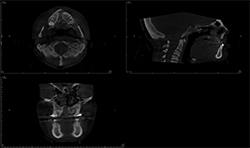

Case 1: 12-year-old boy with delayed eruption of the mandibular left second molar

CBCT images of the same patient (Figs. 2A, 2B, 2C) reveal the lesion extends mesial to the third molar follicle, displacing the thinning buccal cortex. The lesion arises from the cementoenamel junction (CEJ) of the second molar. The inferior alveolar nerve canal is intact. The lesion was treated by surgical removal and submitted for histological examination. The histopathologic diagnosis was a dentigerous cyst.

Fig. 2A

Fig. 2B

Fig. 2C